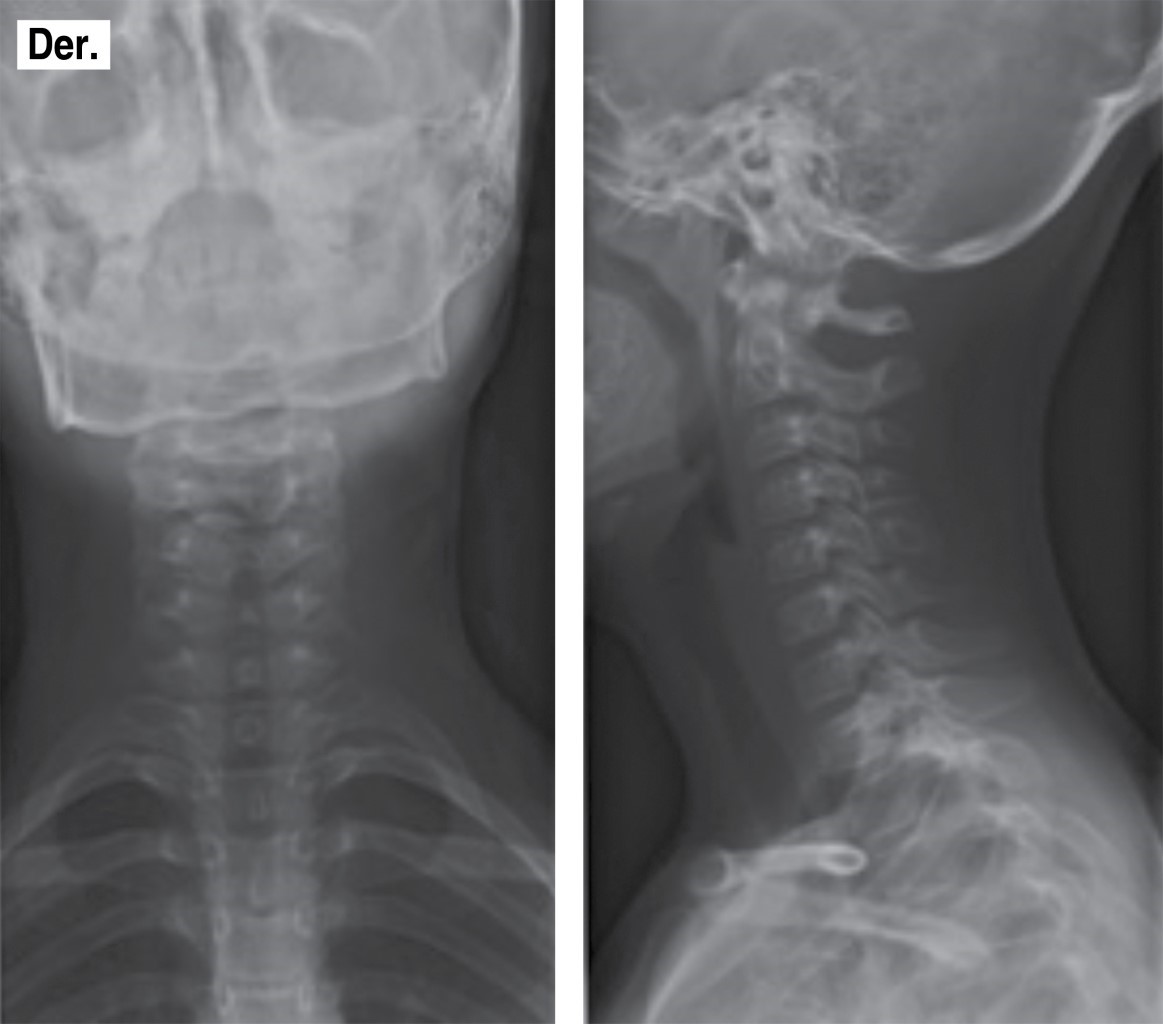

Se obtienen estudios radiográficos en proyecciones anteroposterior y lateral de columna cervical (Figura 2), observando lordosis fisiológica, cuerpos vertebrales con conservación de su altura, adecuados espacios articulares, sin datos de listesis; se observa lesión única a nivel de lámina derecha de quinta vértebra cervical, radiopaca, de bordes bien definidos, de 20 × 15 mm aproximadamente que no infiltra tejidos adyacentes, sin reacción perióstica ni extensión extraósea.

Figura 2